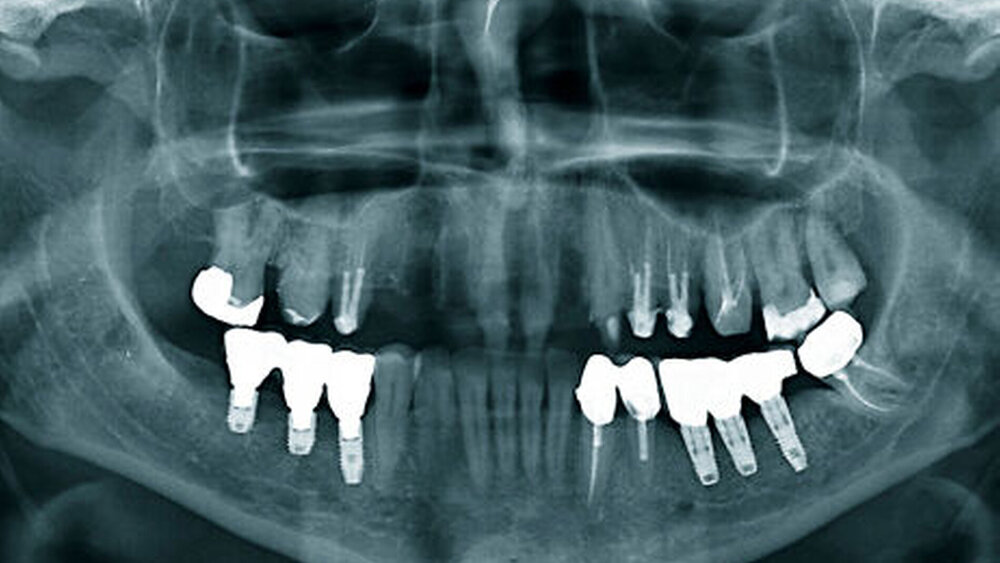

Bei einer jungen zahnlosen Patientin mit schmalem Alveolarkamm wurde klassisch präimplantologisch augmentiert (vestibulärer Knochenblock und BioOss-Anlagerung, Bio- Gide-Membran-Abdeckung) mit vier bis sechs Monaten Einheilzeit. ‧Unglücklicherweise entwickelte sie eine Wunddehiszenz mit ausbleibender Knochenregeneration und Verlust des Augmentats. Eine erneute Augmentation kam für sie wegen der OP-Belastung und einer sich weiter verlängernden Therapiedauer nicht infrage. Als eine mögliche alternative Versorgung stimmte sie der Insertion von drei Profile EV-Implantaten mit abgeschrägter Implantatschulter zu. Die Kontrolluntersuchungen nach zwei und fünf Jahren zeigten eine sehr gute Osseointegration und zudem eine sehr gute stabile periimplantäre Weichgewebssituation ohne zusätzliche peri‧implantäre Weichgewebsver‧dickung, ein Phänomen, so Wagner, das ein typischer Weichgewebevorteil für alle Implantate mit Platform Shift sei, nicht nur für das Profile EV. Als Hauptindikationen für diese anatomischen Implantatformen nannte Wagner

Dass sich Implantate mit abgeschrägter Schulter im Praxisalltag bewähren, belegt eine aktuelle Feldstudie mit Beteiligung von mehr als 20 niedergelassenen Kollegen [1]. Wagner: „Wir haben als Gruppe mehr als 200 TXProfile-Implantate gesetzt, nur zwei gingen verloren. Das ist ein extrem gutes Ergebnis.“ Zudem habe das Profile-Implantat einen beachtlichen positiven Einfluss auf das Weichgewebe, was aber nicht nur auf die Implantatgeometrie, sondern auch auf den Platform Shift zurückzuführen sei. „Rund 40 Prozent der Implantate von Dentsply Sirona Implants, die wir im Unterkieferseitenbereich und der Oberkieferfront setzen, sind inzwischen Profile-Implantate des Astra Tech Implant-Systems.

Sowohl bei Wagner als auch bei Dr. Dr. Rainer S. R. Buch, Wiesbaden/Ingelheim, reduziert sich seit 2005/2006 der relative Anteil an zusätzlich notwendigen Augmentationen, das heißt, die „persönlichen Augmentationskurven“ sinken kontinuierlich. Buch kann in seiner Praxis Augmentationen immer häufiger vermeiden, weil ein Portfolio an verschiedenen Implantat‧designs zur Verfügung steht – durchmesser- und längenreduzierte Implantate und heute auch Implantate mit abgeschrägter Schulter. Auch in seiner Praxis sind mittlerweile nahezu 40 Prozent der bei Dent‧sply Sirona bestellten Astra-Implantate abgeschrägte Profile-EV-Implantate. Die Indikationsausweitungen seien enorm, berichtete er. Nicht nur der seitliche Unterkiefer mit seiner durch Atrophie bedingten typischen Geometrie diene als Einsatzbereich, sondern auch die Oberkieferfront und der zahnlose Unterkiefer.